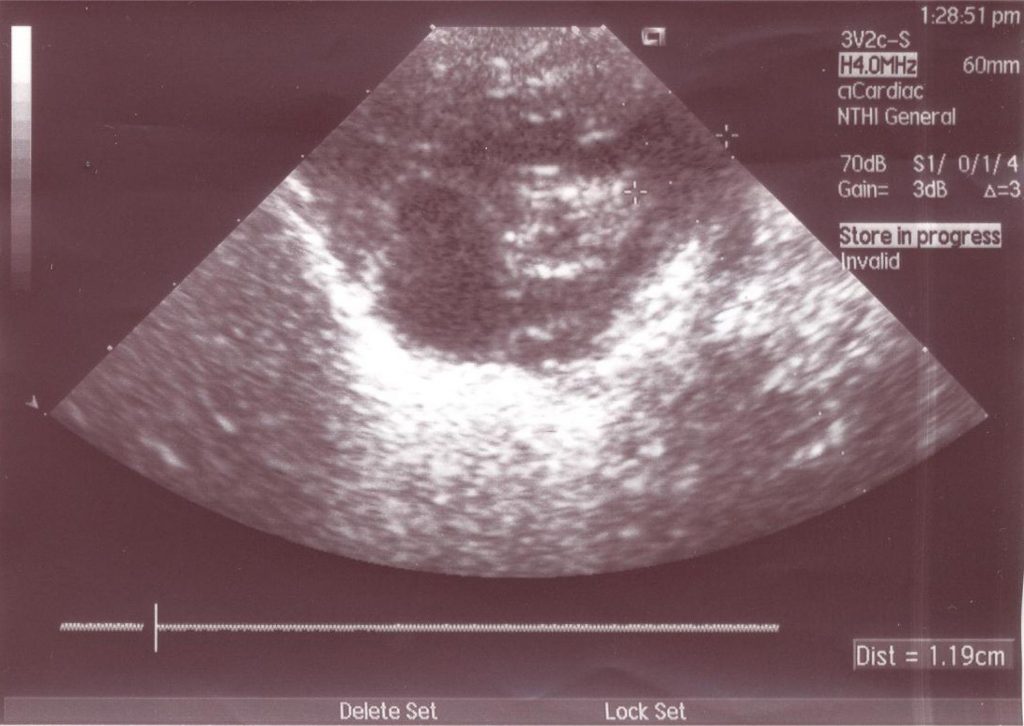

Figura 3

Defeito do septo atrial do tipo Ostium Secundum. Observa-se também aumento do AD e tronco da artéria pulmonar dilatado